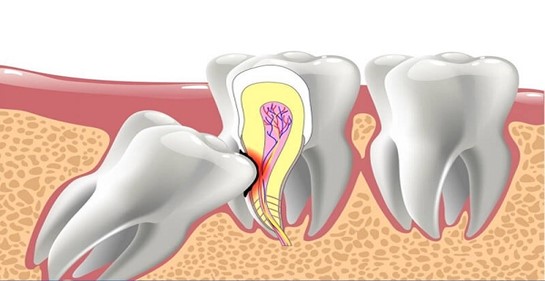

Cùng Nha Khoa Việt Mỹ – Phường Bảy Hiền – “Nâng Niu Nụ Cười Việt” tìm hiểu nhé: Chữa viêm tủy răng là phương pháp loại bỏ phần tủy bị hoại

Cùng Nha Khoa Việt Mỹ – Phường Bảy Hiền – “Nâng Niu Nụ Cười Việt” tìm hiểu nhé: Chữa viêm tủy răng là phương pháp loại bỏ phần tủy bị hoại

Nha Khoa Việt Mỹ “Nâng Niu Nụ Cười Việt – Trụ sở chính Quận 10 xin trả lời như sau: Tổn thương các răng và mô nướu quanh nó: khi răng